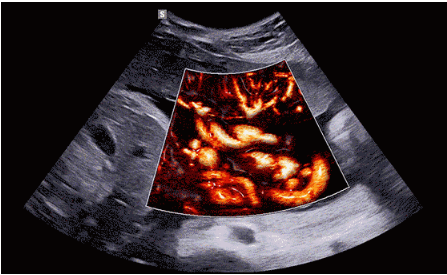

3D/4D成像方面,Hera i 10通過結合先進的圖像渲染技術,著重加強了邊緣和小結構的可視化能力。